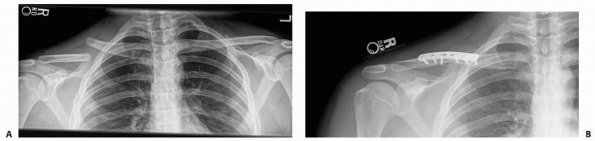

characterize fractures of the medial third of the clavicle and

sternoclavicular injuries. The “serendipity” view, where a broad x-ray

beam with 40 degrees of cephalic tilt projects both clavicles on the

same film, is helpful for evaluating fractures in this portion of the

clavicle (Fig. 17-3).459

By comparing with the uninjured contralateral side, the location of

injury and the degree of displacement often can be determined. However,

this view can be difficult to interpret, especially for mild injuries.

FIGURE 17-3 A. Serendipity view of the medial clavicle. Note inferior displacement of medial end of left clavicle. B. CT confirmed left sternoclavicular posterior dislocation.